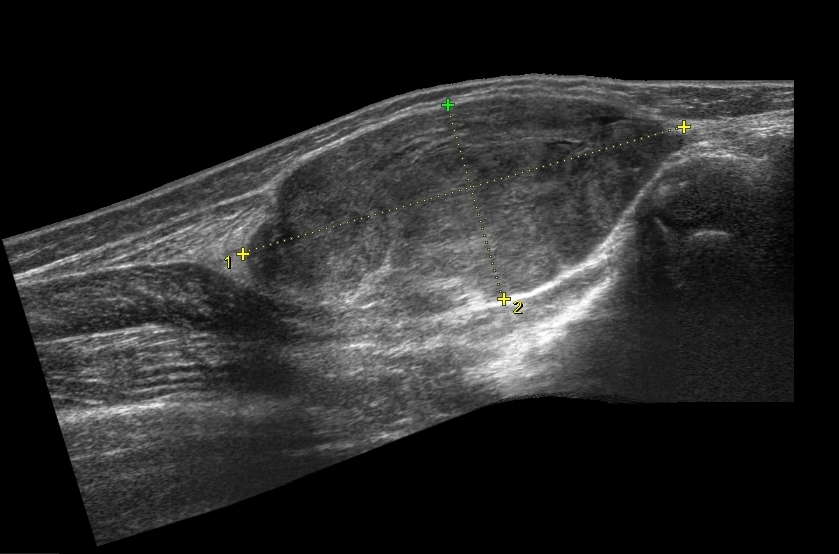

В возрасте 11 месяцев после травмы было отмечено появление образования в мягких тканях в вехней трети. Первично было расценено как гематома, на фоне физиотерапии объем уменьшился, однако через некоторое время отмечено повторное появление образования с постепенным ростом.

В проекции задней поверхности правой голени определяется солидное образование ~70х30х40мм, капсула прослеживается, в структуре дифференцируются жидкостные участки неправильной формы, образование имеет овальную форму,четкие ровные контуры. При ЦДК и ЭК активный кровоток с нарушением архитектуры сосудистого дерева